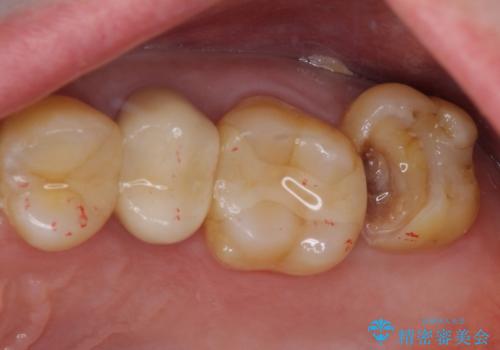

冷たいものがしみる 神経組織の一部を除去した虫歯治療

- 冷たいものにしばしば痛みを感じるとのことで来院された患者様です。

診査をしたところ、レントゲン写真よりとても大きなむし歯があることが分かりました。

虫歯が歯髄腔(神経の部屋)に達している可能性が非常に高かったため、炎症を起こしている神経組織を部分的に切除し、歯根部分の神経組織を保存する治療法が望ましいと考えられました。

虫歯は深くまで進行しており、歯冠部の神経から出血が認められました。神経を部分的に除去したところ出血が治まったので、生体親和性の非常に高いセメントにて充填し、仮封をしました。

欠損歯質は比較的小さかったため、セラミックインレーにて修復治療を行いました。